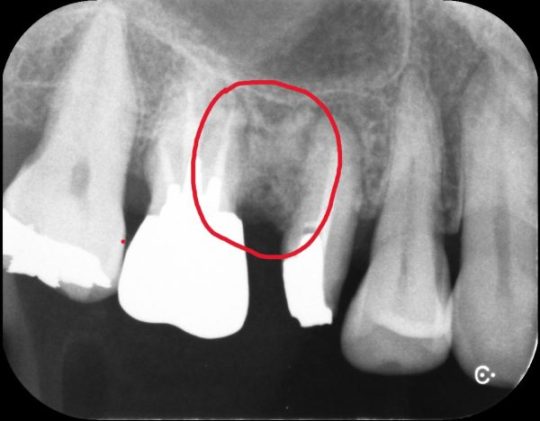

歯と歯の間にひびが入ることも多く、

その場合は目視では確認できないのでレントゲン写真などで確認します。

またレントゲンでも見つけることが難しいことが難しいことが現状です。